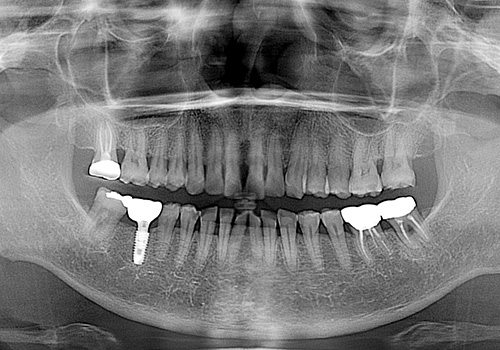

김○인님 임플란트 식립 전

2019년 7월

김○인님 임플란트 식립 후

2022년 8월 -